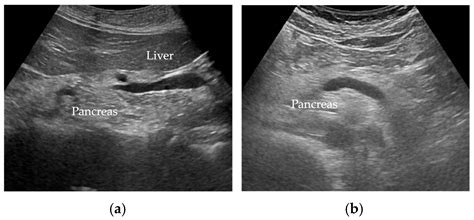

To understand why your ultrasound shows increased echogenicity of the liver, it helps to know how an ultrasound works. An ultrasound machine uses sound waves that bounce off internal organs to create an image. Tissues with different densities reflect these waves differently. A healthy liver typically has a specific texture and brightness on the screen, known as echogenicity. When the liver cells accumulate excess substances—most commonly fat—the sound waves bounce back more intensely, making the organ appear brighter or "hyperechoic" on the monitor compared to the surrounding tissues.

Essentially, this finding is a diagnostic clue, not a specific disease in itself. It acts as a prompt for your healthcare provider to investigate further, as it signals that there may be an infiltration of substances that are changing the liver's natural density.